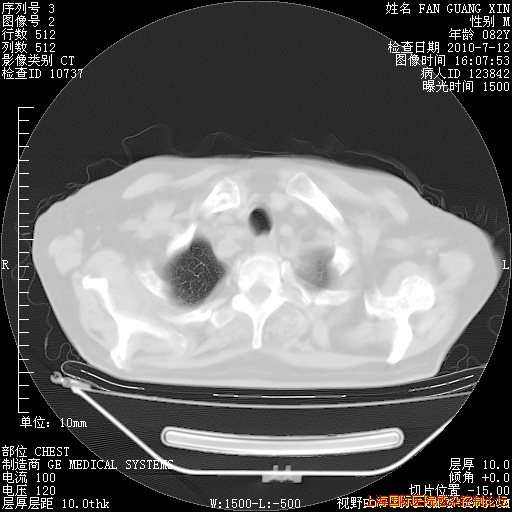

今天复查CT

今天CT